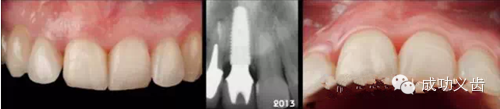

图1.延期种植1,2007年种植修复刚刚完成时的照片。

图2.延期种植2,2014年不论是从照片还是X线上,都显示出种植周围软硬组织稳定,颜色粉嫩!